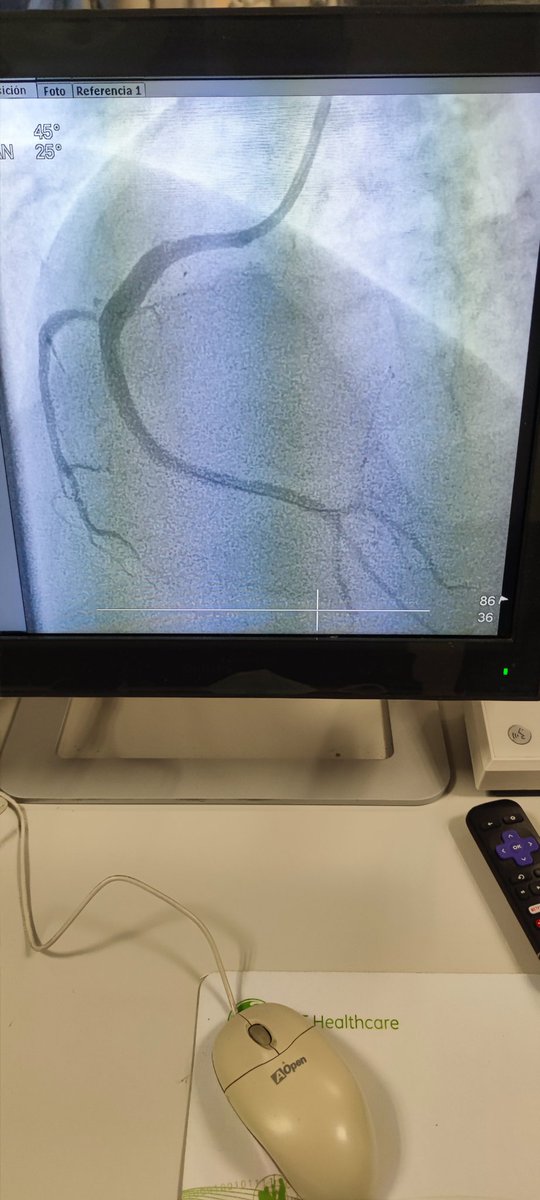

🫀⚡🧔🏻 45a, 🚬intenso, sedentario, obeso, HTA, #SICA #RadialFirst angio CD OTC agudizada TM disección ostial, Fullmetal CD 👌🏼 #MasterTheComplex #PCI #IVUS #Terumo #Azahi #BostonScientific #Medtronic